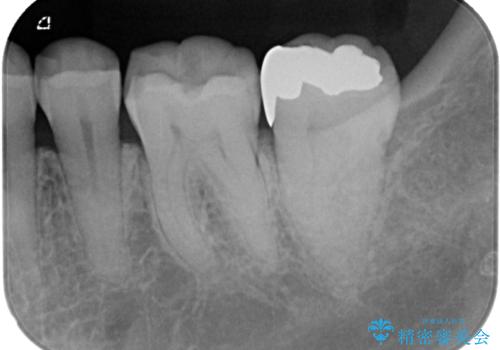

- 銀歯がとれたのでやり替えたいとのことで来院された患者様です。来院時特に症状もなく金属の詰め物(メタルインレー)がとれたのでセラミックの詰め物(セラミックインレー)にやり替えていくことになりました。また患者様のご希望によりひとつ後ろの歯の金属の詰め物(メタルインレー)のやり替えも同時に治療していくことになりました。

拡大鏡視野下で、金属の詰め物(メタルインレー)、保険のプラスチック、虫歯の除去を行い、セラミックインレーに適した形に整えました。

歯と歯の間の虫歯の治療について

歯と歯の間の虫歯をコンポジットレジンや保険のメタルインレーで治すと段差ができたりして清掃性が悪くなるので、セラミックインレー修復やゴールドインレー修復などの適合の良い詰め物で治療することをオススメします。